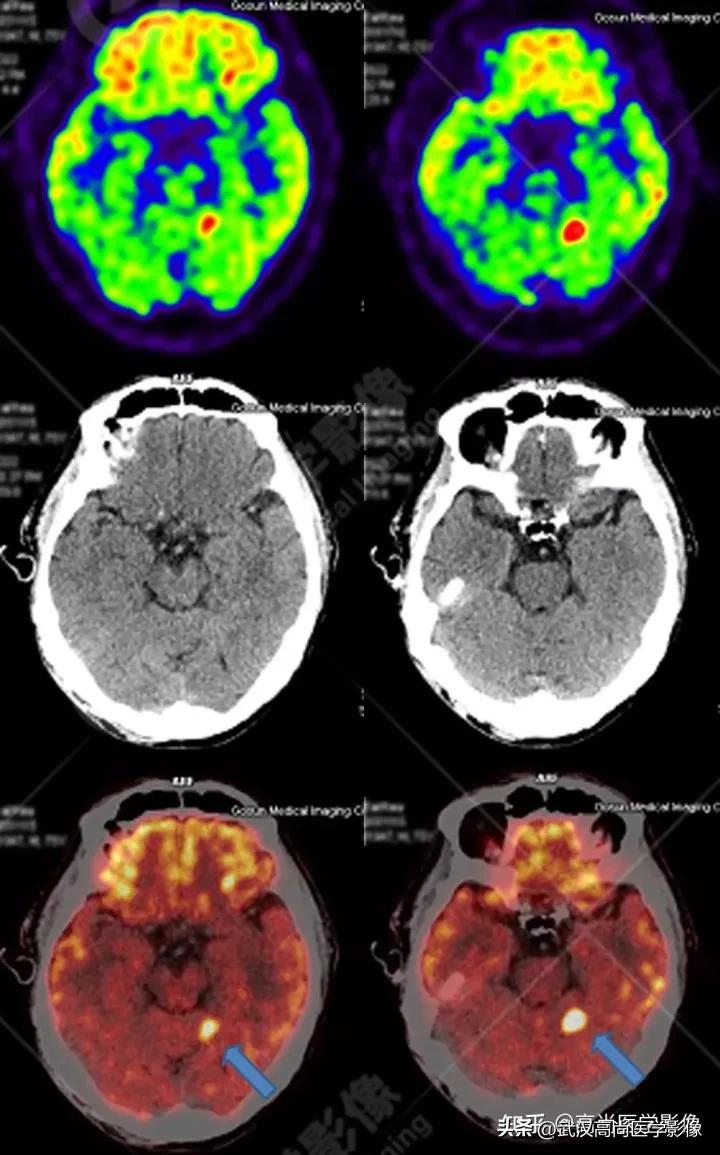

男性63岁,头痛查体。

脑部影像表现: 脑内多发大小不一的高密度结节,伴瘤周水肿,FDG高摄取,SUVmax20.1。

常见脑转移瘤典型特点: 小肿瘤大水肿,“人小鬼大”。